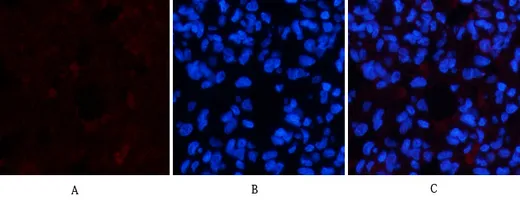

Active Caspase-3(5E1)Mouse Monoclonal Antibody

Cat: AMM06555

Size1:50μL Price1:$128

Size2:100μL Price2:$230

Size3:200μL Price3:$380

Application:IF-P,IF-F,ICC/IF,WB,IP,IHC-P

Reactivity:Human,Mouse,Rat,Chicken

Conjugate:Unconjugated

Optional conjugates: Biotin, FITC (free of charge). See other 26 conjugates.

Gene Name:CASP3